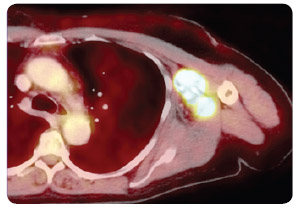

Obr. 1 PET vyšetření před zahájením léčby ipilimumabem – metastázy v levé axile a paži.Ipilimumab je IgG1 lidská monoklonální protilátka proti receptoru CTLA-4. Přestože je její účinnost zkoušena u mnoha malignit, zatím nejlepších výsledků dosáhl výzkum právě při léčbě maligního melanomu. Proběhla řada klinických studií fáze II, kde byl ipilimumab zkoušen v různých léčebných režimech (monoterapie, kombinace s vakcínami nebo chemoterapií) a v různých dávkách (0,3 mg/kg, 3 mg/kg, 10 mg/kg) [7, 8].

V roce 2010 byly publikovány výsledky první velké randomizované multicentrické studie fáze III u pacientů s neresekabilním melanomem III. a IV. klinického stadia předléčených chemoterapií. Pacienti byli randomizováni do tří ramen, v nichž nemocní dostávali ipilimumab, ipilimumab v kombinaci s vakcínou gp100 nebo samotnou vakcínu gp100. IpilimumObr. 2 PET vyšetření 12 týdnů po zahájení léčby ipilimumabem – téměř kompletní remise.   CT – počítačová tomografie; PET – pozitronová emisní tomografieab byl podáván v dávce 3 mg/kg v 90minutové nitrožilní infuzi každé tři týdny, celkem čtyřikrát. Medián OS v rameni s ipilimumabem v kombinaci s vakcínou gp100 byl 10,0 měsíce, v rameni se samotným ipilimumabem 10,1 měsíce a se samotnou vakcínou gp100 pak 6,4 měsíce.

Rozdíly v přežití mezi pacienty léčenými samotným ipilimumabem a vakcínou byly statisticky signifikantní (p = 0,003). Léčebná odpověď (CR a PR) v rameni se samotným ipilimumabem byla zaznamenána u 10,9 %. U dalších 17,5 % pacientů bylo dosaženo stabilizace onemocnění. Většina nežádoucích účinků studiové léčby byla způsobena nadměrnou aktivitou imunitního systému. K nejčastěji postiženým orgánům patřila kůže a gastrointestinální trakt. Nejčastějším imunitně podmíněným Obr. 3 Fúze PET a CT vyšetření před zahájením léčby ipilimumabem – metastázy v levé axile a paži.nežádoucím účinkem byl průjem (až 30 % pacientů). Při rozvoji vážnější toxicity (stupeň 3 a 4) je doporučeno okamžitě začít podávat vysoké dávky kortikosteroidů, eventuálně, v případě jejich neúčinnosti, pacienty zavčas převést na jinou imunosupresivní léčbu (infliximab, mykofenolát mofetil) [9].

Výsledky druhé velké klinické studie fáze III u pokročilého melanomu byly prezentovány a publikovány v roce 2011. Tato klinická studie byla zaměřena Obr. 4 Fúze PET a CT vyšetření 12 týdnů po zahájení léčby ipilimumabem – téměř kompletní remise.na chemoterapií nepředléčené pacienty (první linie paliativní systémové léčby). Ipilimumab zde byl podáván ve vyšší dávce, a sice 10 mg/kg. Pacienti byli randomizováni do dvou ramen. V prvním rameni studie byl podáván ipilimumab 10 mg/kg (4krát á 3 týdny) v kombinaci s dakarbazinem (850 mg/m2), ve druhém rameni dostávali nemocní dakarbazin v monoterapii (850 mg/m2). Mediány OS v ramenech s léčebnou kombinací ipilimumab-dakarbazin byly 11,2 měsíce oproti 9,1 měsíce v rameni s dakarbazinem, jednoleté přežití 47,3 % vs. 36,3 %, dvouleté 28,5 % vs. 17,9 %, tříleté 20,8 % vs. 12,2 % a čtyřleté přežití 19 % vs. 9,6 % (p < 0,001). Četnost léčebných odpovědí (CR + PR) byla v rameni s kombinací ipilimumab-dakarbazin 15,2 %, v rameni s dakarbazinem samotným 10,3 % (p = 0,09). Trvání léčebné odpovědi bylo ale při monoterapii ipilimumabem signifikantně delší (19,3 vs. 8,1 měsíce; p = 0,03). Nejčastějším imunitně podmíněným nežádoucím účinkem stupně 3 a 4 byla v rameni s ipilimumabem překvapivě hepatitida, která se vyskytla v 31,6 %, zatímco v rameni s dakarbazinem se objevila pouze ve 2,4 %. Příčinou byla pravděpodobně potenciace této toxicity dakarbazinem [10]. Naše vlastní zkušenosti s léčbou ipilimumabem ukazují obr. 1, 2, 3, 4.